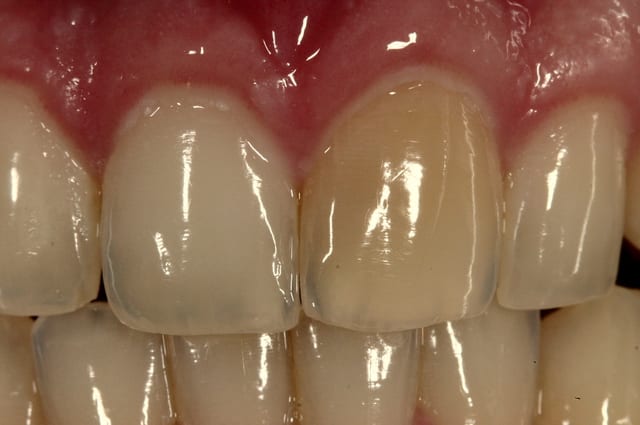

Tu peux faire une gouttière unitaire et utiliser du peroxyde de carbamide à 15% (et pas acid) en port nocturne.

Exemple d'un cas.

--

Dr Cingulum

-----Ancien interné----

----Attaché à l'apex----

http://www.clinic-all.fr/ formation par passion